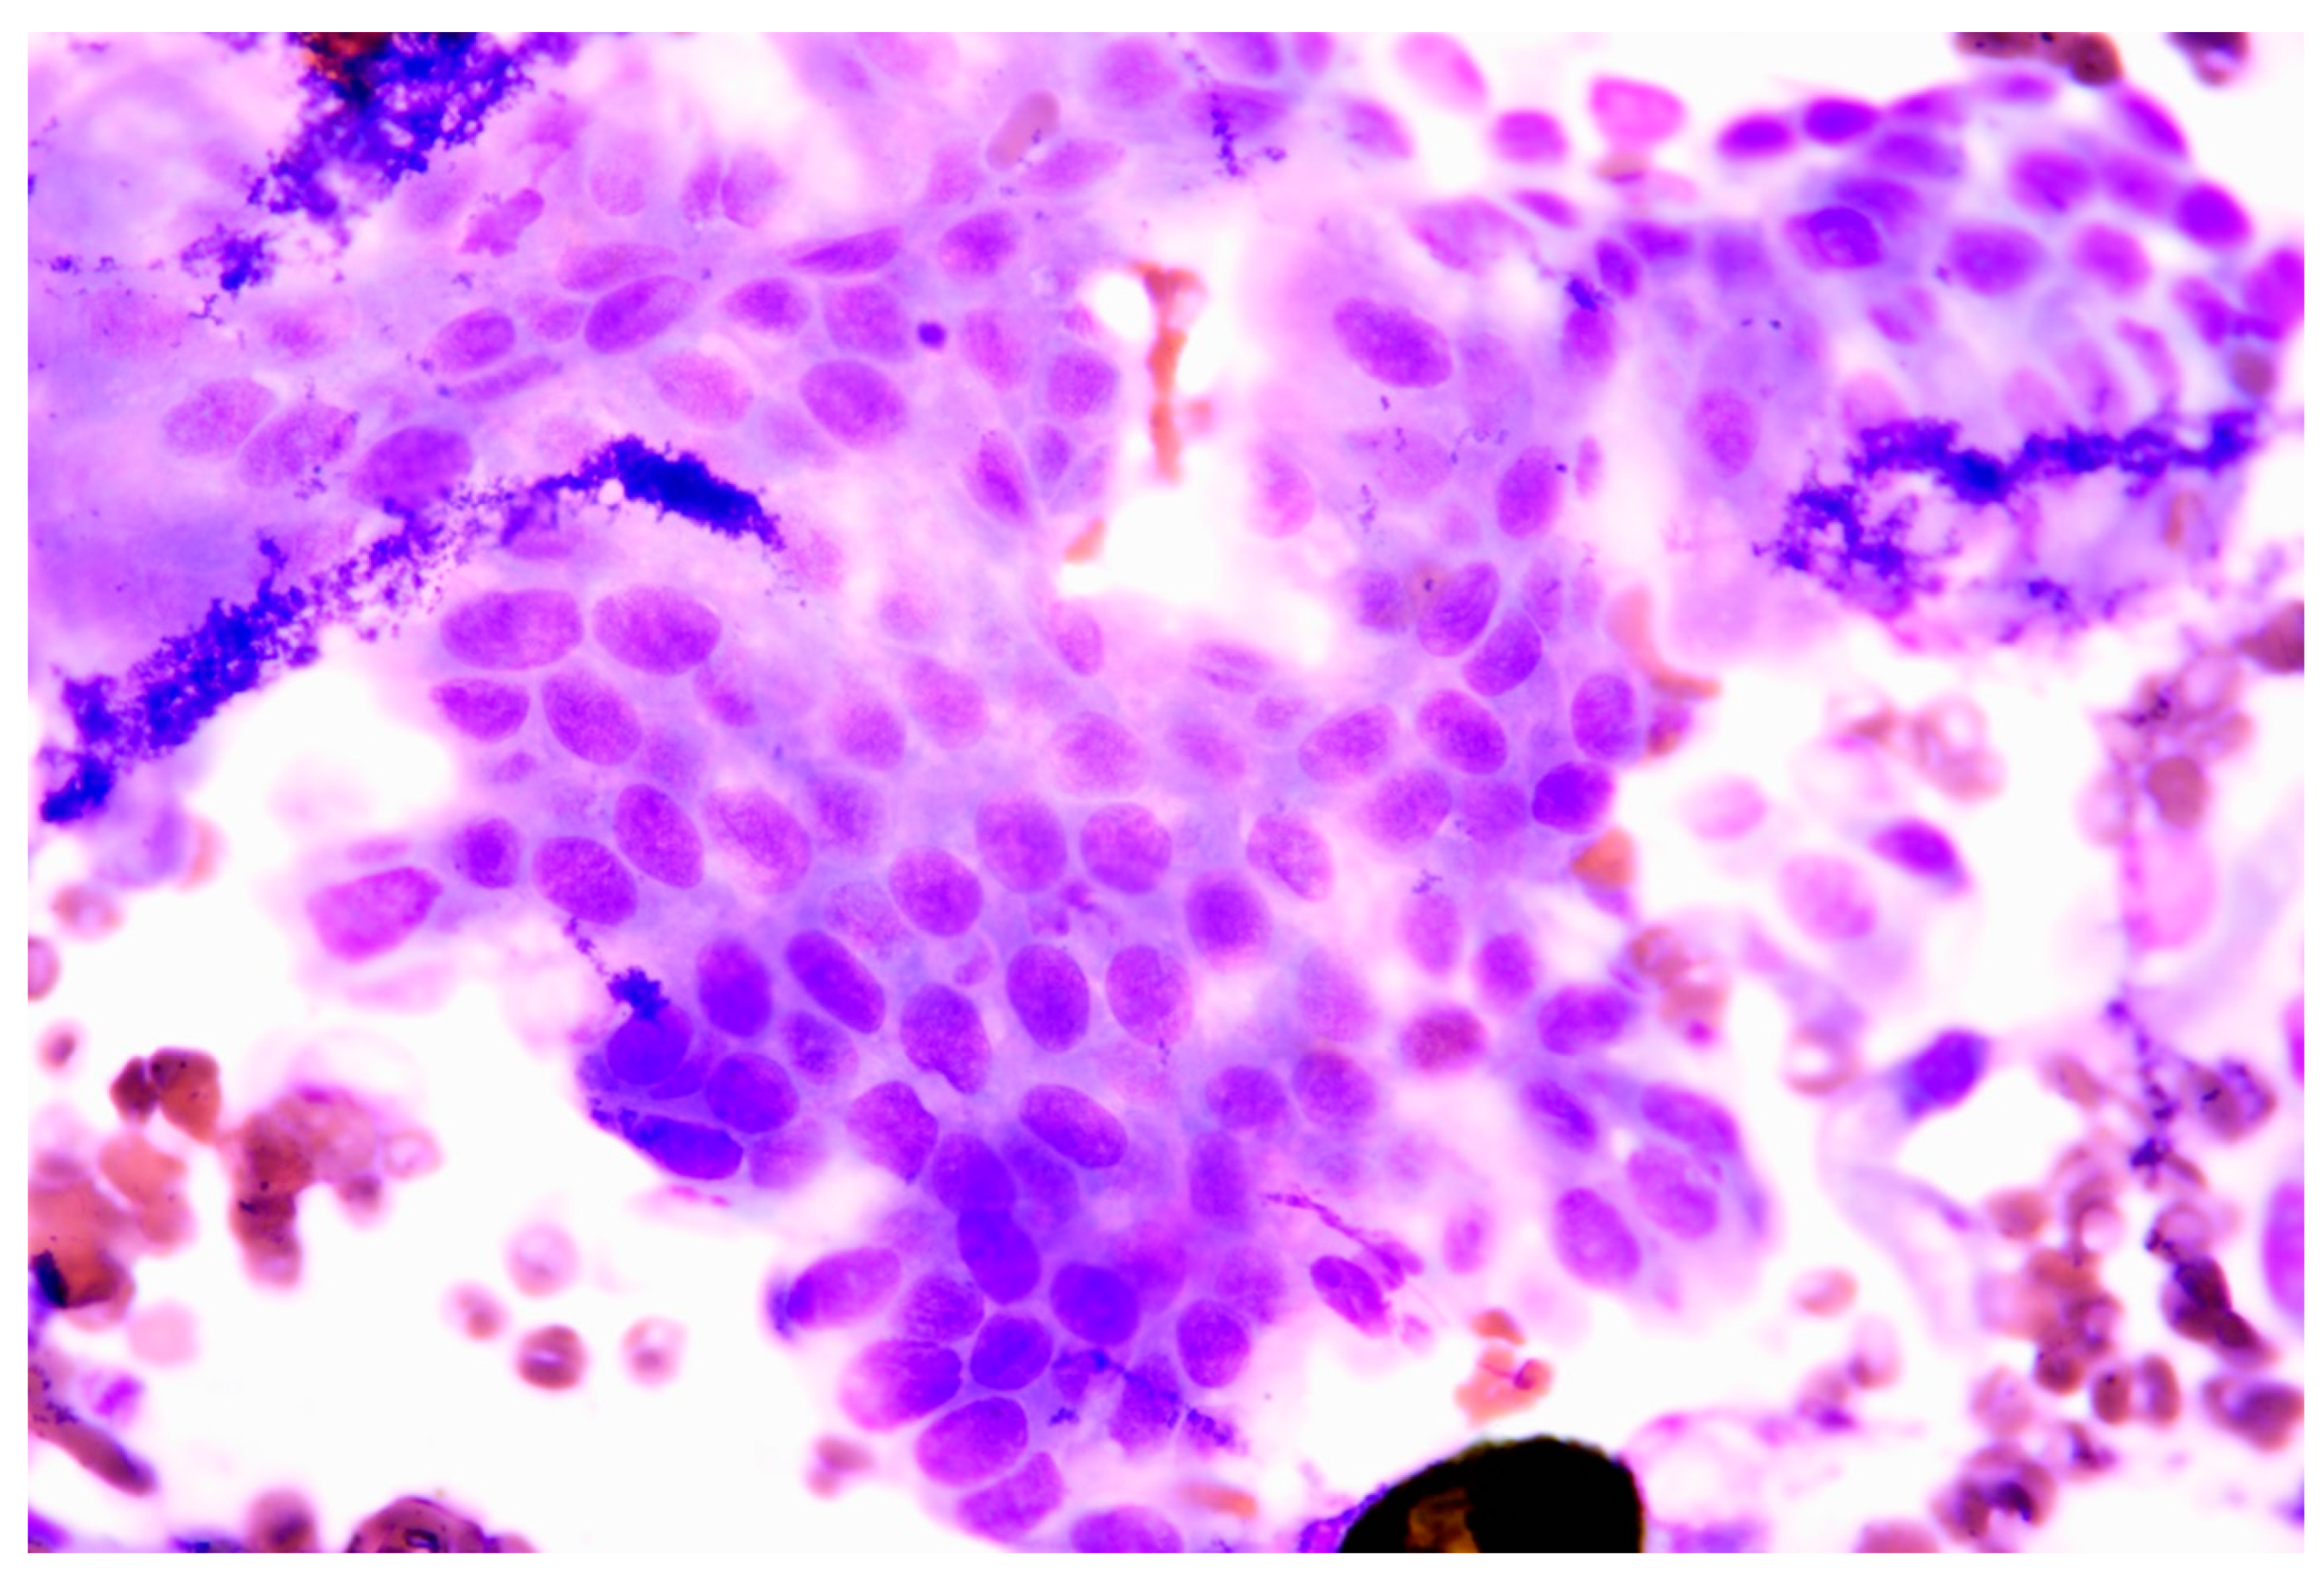

Figure 2. (A,B,C). Axial view of CT scan of skull. The size of the tumor decreased significantly after radiation/chemotherapy compared with before radiation/chemotherapy, after radiation, and before chemotherapy (Asteroid).